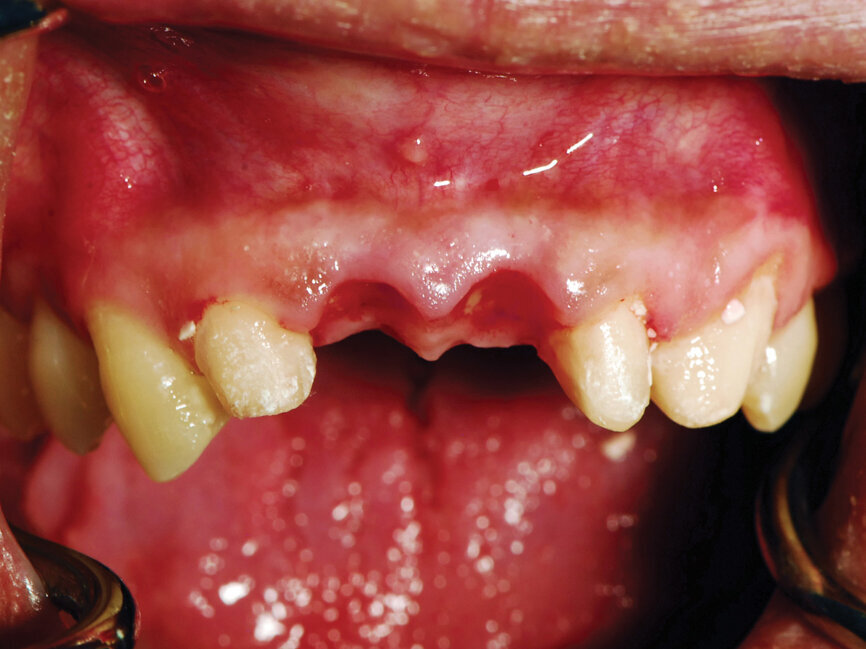

A 30-year-old female patient presented with severely malposed maxillary central incisors tipped facially and a desire for esthetic improvement. A CBCT was taken and minimal bone was noted present over the facial of the central incisors.

Options for treatment were presented to the patient that included: orthodontics to correct esthetics or extraction of the central incisors, placement of implants at these sites and restorations on the anterior teeth. The patient indicated she did not wish to pursue an orthodontic treatment option because of the time involved.

The patient presented for surgery and the central incisors were atraumatically extracted under local anesthetic. The adjacent teeth were prepared for crowns, which would support a provisional bridge during the healing/integration period. A 4-mm wide, 24-degree Co-Axis Implant (Keystone Dental, Burlington, Mass.) was placed into the osteotomy at each central incisor orienting the prosthetic axis to a vertical position, while the implant’s body followed the trajectory of the premaxilla.

A healing screw was placed and osseous graft material (NovaBone, Alachua, Fla.) placed on the facial to thicken the resulting bone. The soft tissue was closed with resorbable PGA sutures. A stent created over the wax-up of the study models that had been modified was filled with an auto-cure provisional resin (Perfectemp 10, DenMat, Lompoc, Calif.) and seated over the anterior and allowed to set. Upon setting, the stent with provisional was removed intraorally and trimmed and polished. At the implant sites, the material was shaped to a bullet shape to assist in forming an emergence profile in the soft tissue and preserve the papillas.

Six months post-implant placement, the provisional bridge was removed and preservation of the papillas was confirmed with a natural emergence profile within soft tissue (Figs. 6,7). Local anesthetic was administered. The Picasso Lite+ diode laser was set at 2.5 watts in continuous mode with an initiated tip and at the center of the depression in the soft tissue above the implants cover screw and moved in a circular motion moving outward until the entire cover screw was exposed (Fig. 8).